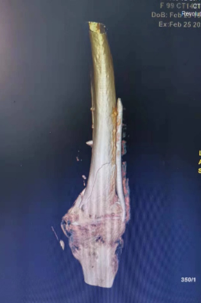

为了尽可能地缩短手术时间、减少术中出血、降低手术创伤,保障手术安全,雷青、二十三病室主任陈松、副主任医师王康及手术部、麻醉科团队密切配合,在全麻监护下,经皮置入Liss钢板,骨折端闭合复位,透视下确认骨折复位情况及内固定位置后螺钉固定。

整台手术一气呵成,仅用时20分钟即完成内固定置入,术中失血约10毫升,术中老人各项生命体征平稳。